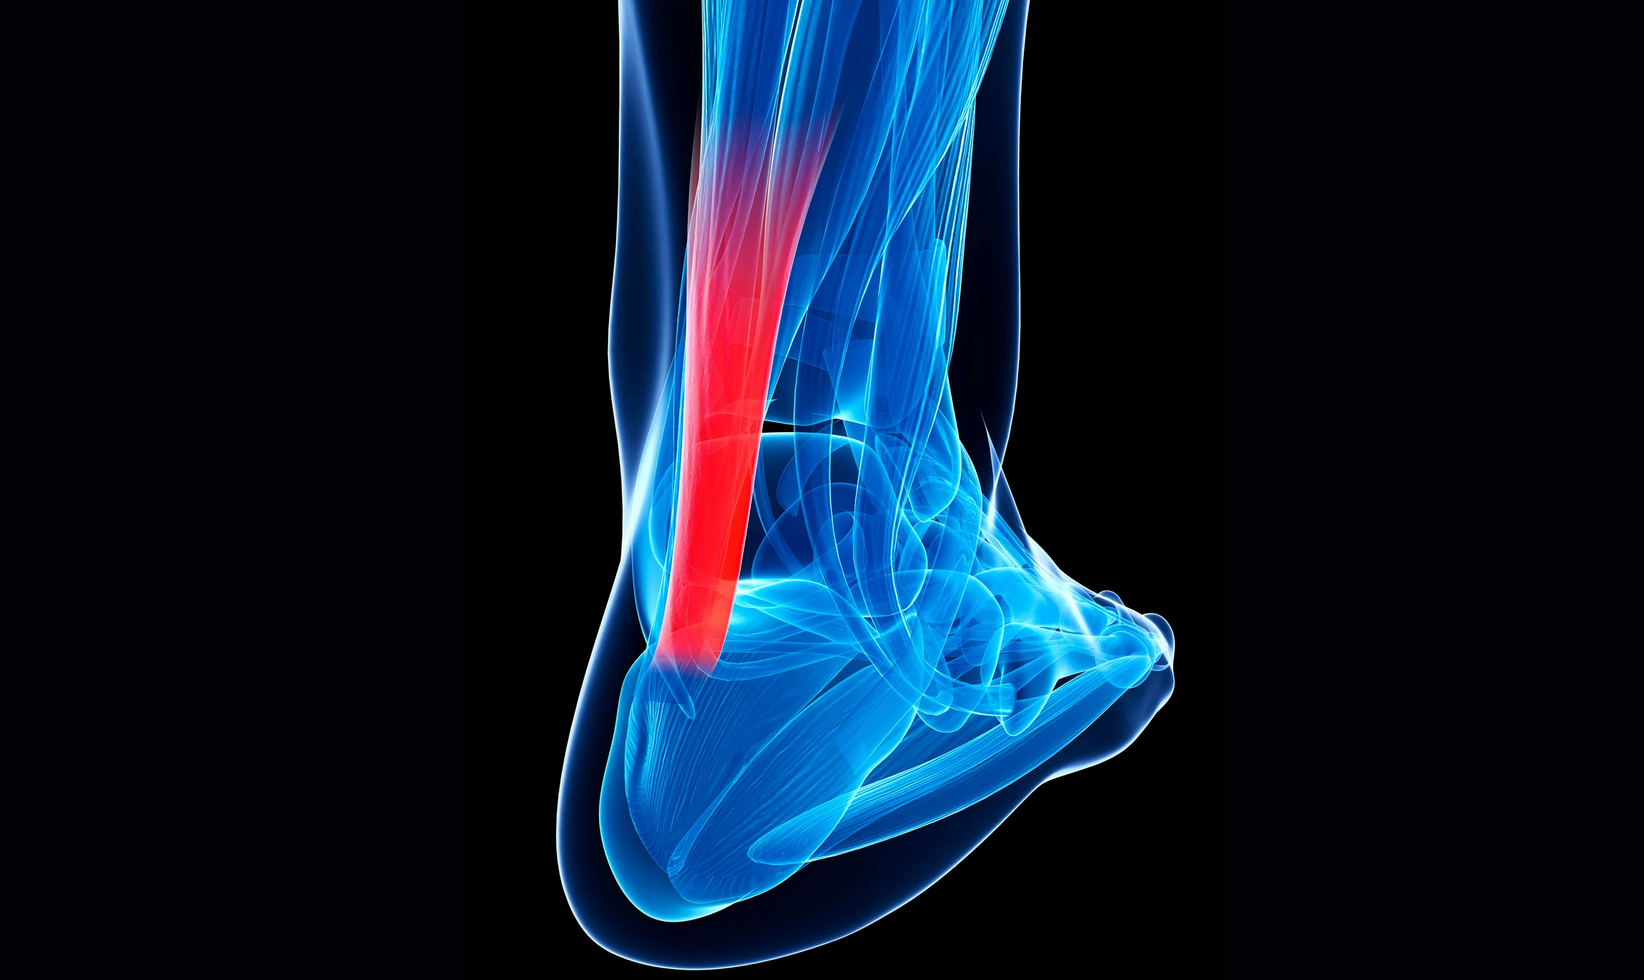

QUÉ ES UN ESGUINCE DE TOBILLO Un esguince de tobillo es una lesión común que sucede cuando los ligamentos que estabilizan las articulaciones del tobillo se estiran más allá de su rango normal o se rompen, generalmente como resultado de una torcedura o un movimiento brusco. Suele producirse al pisar mal, girar el pie de forma repentina o al caer con el pie en mala posición. Los síntomas típicos incluyen dolor, hinchazón, hematoma e inestabilidad . La gravedad del esguince varía según el grado de daño en los ligamentos y el tratamiento puede ir desde reposo y fisioterapia hasta inmovilización temporal, dependiendo del caso. CLASIFICACIÓN SEGÚN LOS LIGAMENTOS AFECTADOS: 1-ESGUINCE LATERAL EXTERNO: Cualquier ligamento del cuerpo es susceptible de sufrir un esguince, pero concretamente en el tobillo el más habitual es el esguince lateral externo en el que se fuerza el pie a una inversión (el pie gira hacia adentro) comprometiendo ligamentos que conectan las articulaciones del hueso peroné con el astrágalo y el calcáneo: Ligamento peroneoastragalino anterior (LPAA) Ligamento peroneocalcáneo (LPC) Ligamento peroneoastragalino posterior (LPAP) Ligamento talocalcáneo lateral (conecta astrágalo y calcáneo) 2-ESGUINCE MEDIAL (INTERNO) Aunque el esguince lateral externo es el más habitual, también puede generarse esguince en los ligamentos mediales (internos) o incluso en los ligamentos de la sindesmosis , menos frecuentes pero importantes. El esguince medial interno afecta al ligamento deltoideo , que es un complejo ligamentoso grueso y fuerte en la cara interna del tobillo, formado por 3 fascículos; (tibioescafoideo, tibiocalcáneo y tibiotalar posterior superficial), este complejo ligamentoso conecta la tibia con el astrágalo, el calcáneo y el escafoides, por lo que estabiliza tanto la articulación tibioperoneoastragalina como otras articulaciones del retropié. ARTICULACIONES IMPLICADAS: Tibiotalar medial (tibiotalar deltoidea) Tibiocalcánea Tibioescafoidea 3-ESGUINCE DE LA SINDESMOSIS (esguince alto del tobillo): Afecta a los ligamentos que mantienen unidos la tibia y el peroné en su parte distal y son los siguientes: Ligamento tibio-peroneo anterior inferior Ligamento tibio-peroneo posterior inferior Ligamento interóseo o membrana interósea distal

El masaje transverso profundo es una técnica de masaje diseñada por James Cyriax. La técnica centra el tratamiento en el punto exacto de la lesión mediante la aplicación de un masaje de forma transversal a las fibas lesionadas, resultando eficaz para lesiones en músculos, tendones y ligamentos. Esta técnica de masaje sigue las siguientes bases de tratamiento: Todo dolor proviene de una alteración del tejido diana; (tendones, músculos y ligamentos). Toda sesión de MTP debe llegar a dicha alteración, para lo cual es necesario localizar exactamente el punto de origen de la lesión. Todo tratamiento debe producir un efecto beneficioso sobre la alteración del tejido. Como ya hemos indicado, los tejidos candidatos a la aplicación de la técnica son fibras musculares, tendones y ligamentos.